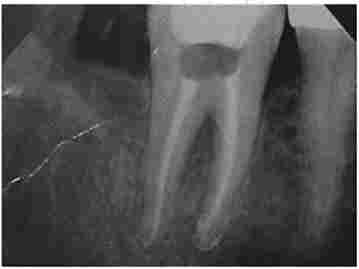

друге відвідування пацієнта. Видаляють тимчасову пломбу, пломбувальний матеріал з кореневого каналу. Канали обробляють і пломбують до рівня фізіологічного звуження верхівки кореня (рис. 6.3), реставрують коронку зуба. Перевіряють оклюзійні контакти. Після лікування пацієнт знаходиться під наглядом стоматолога з періодичним рентгенологічним контролем (рис. 6.4).

Радіовізіограмма зуба 4.6. Контроль пломбування гутаперчевими штифтами кореневих каналів

Мал. 6.3. Радіовізіограмма зуба 4.6. Контроль пломбування гутаперчевими штифтами кореневих каналів

Радіовізіограмма зуба 4.6. Контрольний огляд через 6 МСС

Мал. 6.4. Радіовізіограмма зуба 4.6. Контрольний огляд через 6 МСС.